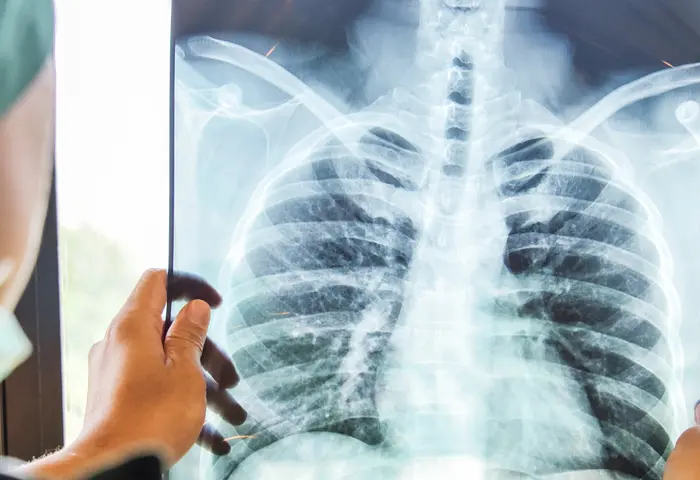

La tuberculosis puede afectar diferentes órganos, la más común de las conductas es la pulmonar, caracterizada por las tos y expectoración mayor de 15 días, pérdida de peso, fiebre y sudoración nocturna.